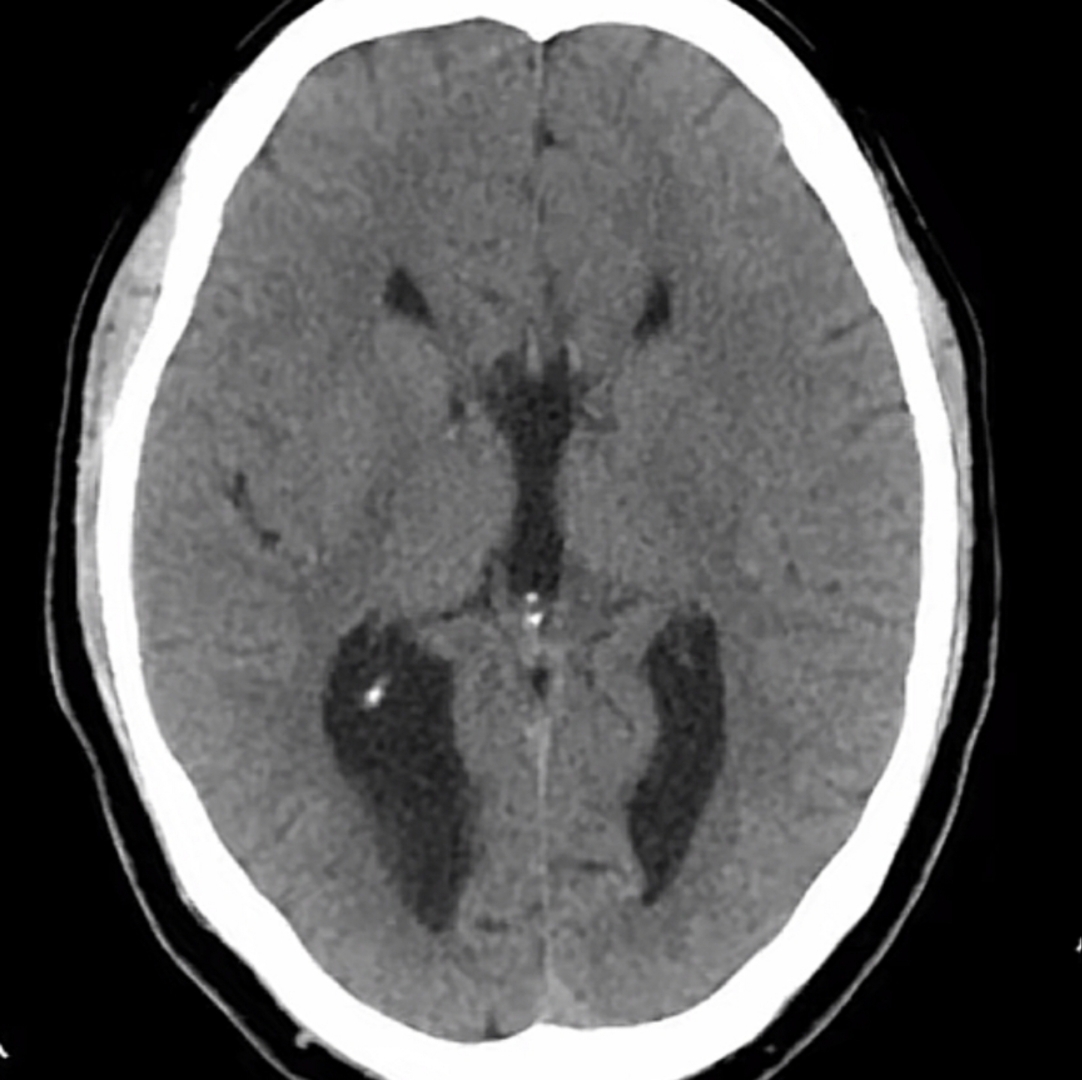

颅脑ct示,右侧额顶深部胼胝体压